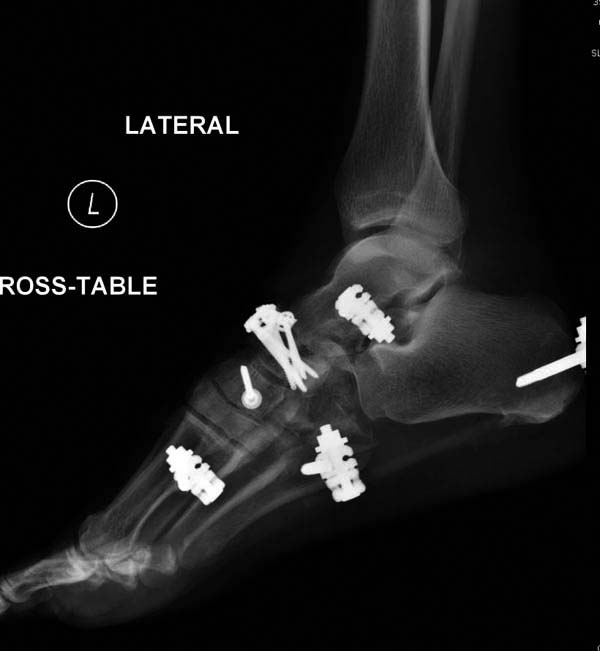

После спадения отека вариантов фиксации много, включая мининвазивную технику, но данный случай закончили установкой простого аппарата Илизарова.

Через три дня оперирована стопа и для нейтрализации сил колонн оставили наружный фиксатор.